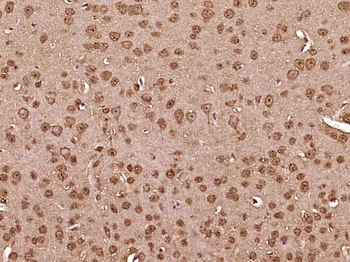

RARB Rabbit Polyclonal Antibody [orb11327]

FC, ICC, IF, IHC-Fr, IHC-P, WB

Bovine, Canine, Gallus, Porcine, Rat

Human, Mouse

Rabbit

Polyclonal

Unconjugated

50 μl, 100 μl, 200 μlTIG2 Rabbit Polyclonal Antibody [orb11481]